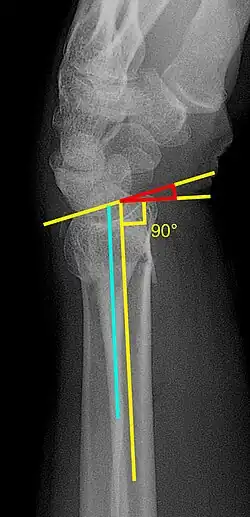

Various kinds of information can be obtained from X-rays of the wrist:[5]

Lateral view

- Carpal malalignment - A line is drawn along the long axis of the capitate bone and another line is drawn along the long axis of the radius. If the carpal bones are aligned, both lines will intersect within the carpal bones. If the carpal bones are not aligned, both lines will intersect outside the carpal bones. Carpal malignment is frequently associated with dorsal or volar tilt of the radius and will have poor grip strength and poor forearm rotation.[5]

- Tear drop angle - It is the angle between the line that pass through the central axis of the volar rim of the lunate facet of the radius and the line that pass through the long axis of the radius. Tear drop angle less than 45 degrees indicates displacement of lunate facet.[5]

- Antero-posterior distance (AP distance) - Seen on lateral X-ray, it is the distance between the dorsal and volar rim of the lunate facet of the radius. The usual distance is 19 mm.[5] Increased AP distance indicates the lunate facet fracture.[8]

- Volar or dorsal tilt - A line is drawn joining the most distal ends of the volar and dorsal side of the radius. Another line perpendicular to the longitudinal axis of the radius is drawn. The angle between the two lines is the angle of volar or dorsal tilt of the wrist. Measurement of volar or dorsal tilt should be made in true lateral view of the wrist because pronation of the forearm reduces the volar tilt and supination increases it. When dorsal tilt is more than 11 degrees, it is associated with loss of grip strength and loss of wrist flexion.[5]

Posteroanterior view

- Radial inclination - It is the angle between a line drawn from the radial styloid to the medial end of the articular surface of the radius and a line drawn perpendicular to the long axis of the radius. Loss of radial inclination is associated with loss of grip strength.[5]

- Radial length - It is the vertical distance in millimetres between a line tangential to the articular surface of the ulna and a tangential line drawn at the most distal point of radius (radial styloid). Shortening of radial length more than 4mm is associated with wrist pain.[5]

- Ulnar variance - It is the vertical distance between a horizontal line parallel to the articular surface of the radius and another horizontal line drawn parallel to the articular surface of the ulnar head. Positive ulnar variance (ulna appears longer than radius) disturbs the integrity of triangular fibrocartilage complex and is associated with loss of grip strength and wrist pain.[5]